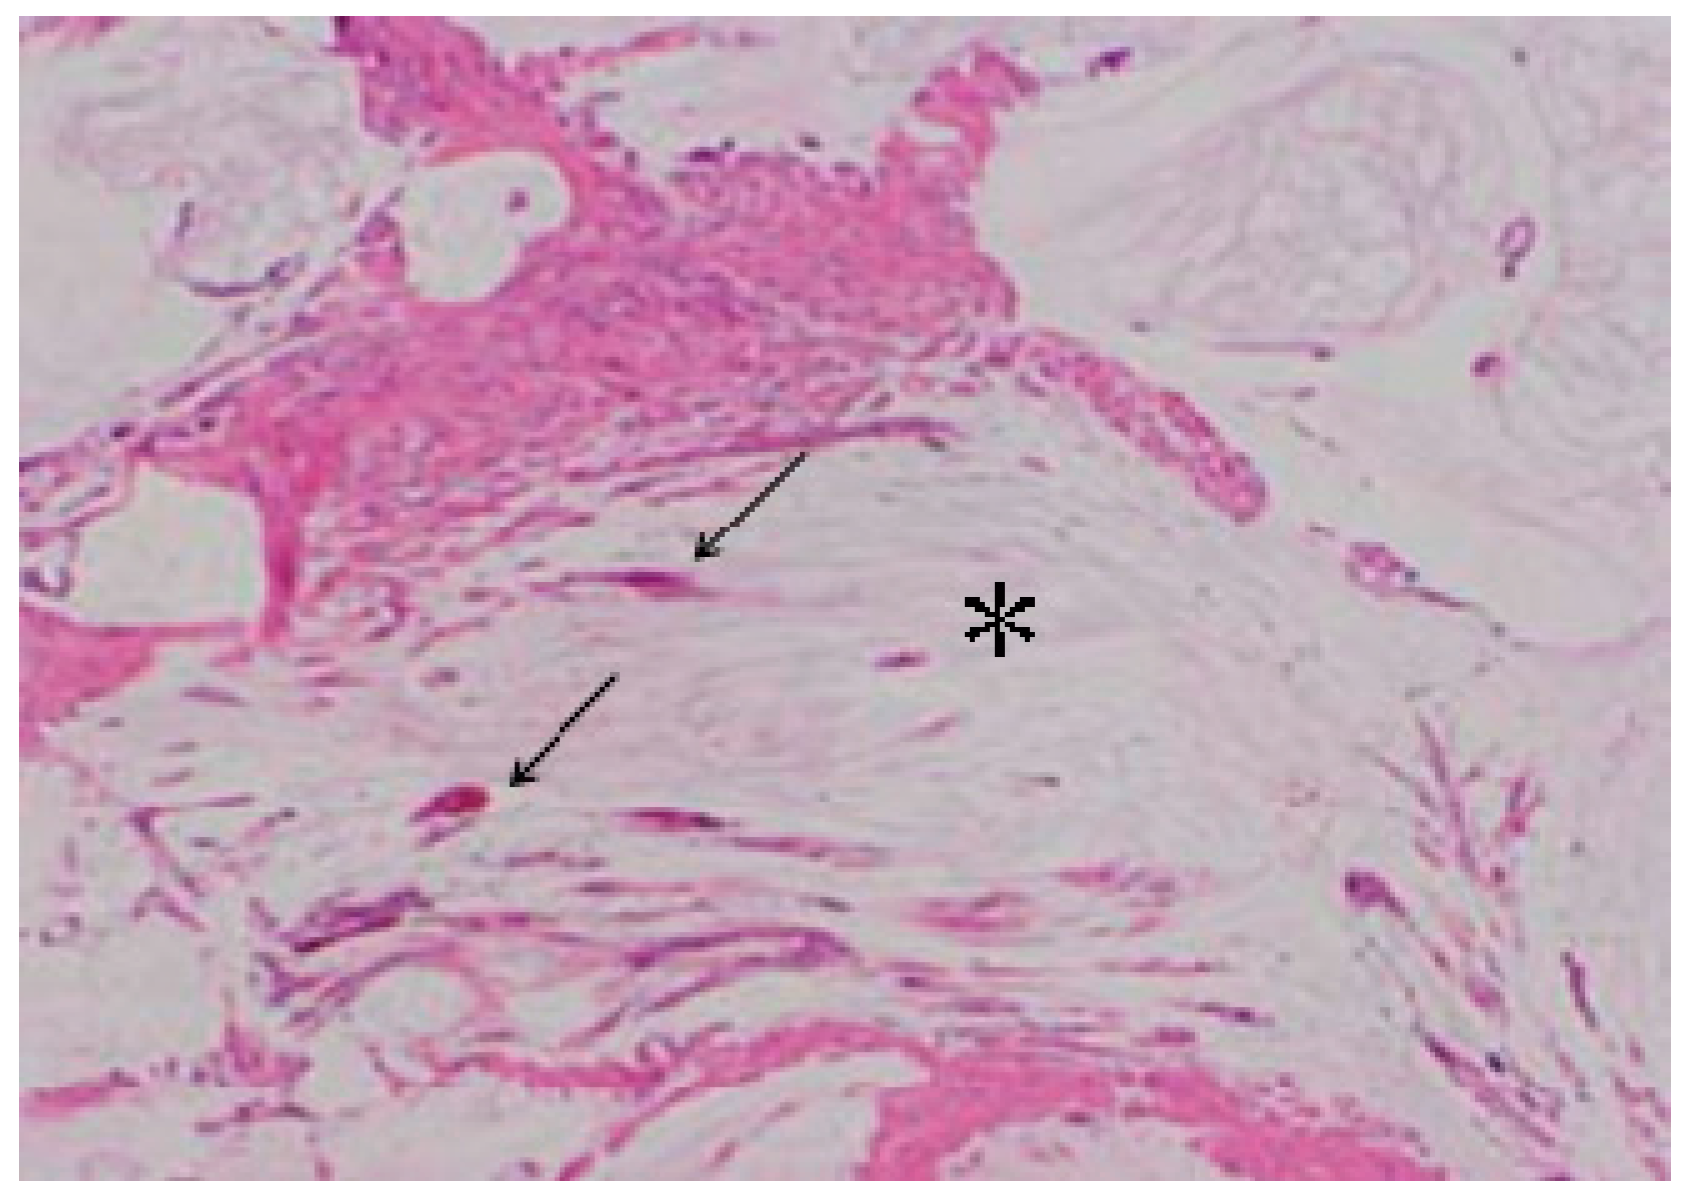

3.2. ALA PDD in Experimental PM

- Yonemura, Y.; Canbay, E.; Ishibashi, H.; Nishino, E.; Endou, Y.; Sako, S.; Ogura, S. 5-aminolevulinic acid fluorescence in detection of peritoneal metastases. Asian Pac. J. Cancer Prev. 2016, 17, 2271–2275. [Google Scholar] [CrossRef] [PubMed]

- Canis, M.; Botchorishvili, R.; Berreni, N.; Manhes, H.; Wattiez, A.; Mage, G.; Pouly, J.L.; Bruhat, M.A. 5-amininolevulinic acid-induced (ALA) fluorescence for the laparoscopic diagnosis of peritoneal metastasis. An experimental study. Sur. Endoscopy. 2001, 15, 1184–1186. [Google Scholar] [CrossRef] [PubMed]

- Hornung, R.; Major, A.L.; McHale, M.; Liaw, L.H.; Sabiniano, L.A.; Tromberg, B.J.; Berns, M.W.; Tadir, Y. In vivo detection of metastatic ovarian cancer by means of 5-aminolevulinic acid-Induced fluorescence in a rat model. J. Am. Assoc. Gynecol. Laparoscopist. 1998, 5, 141–148. [Google Scholar] [CrossRef]